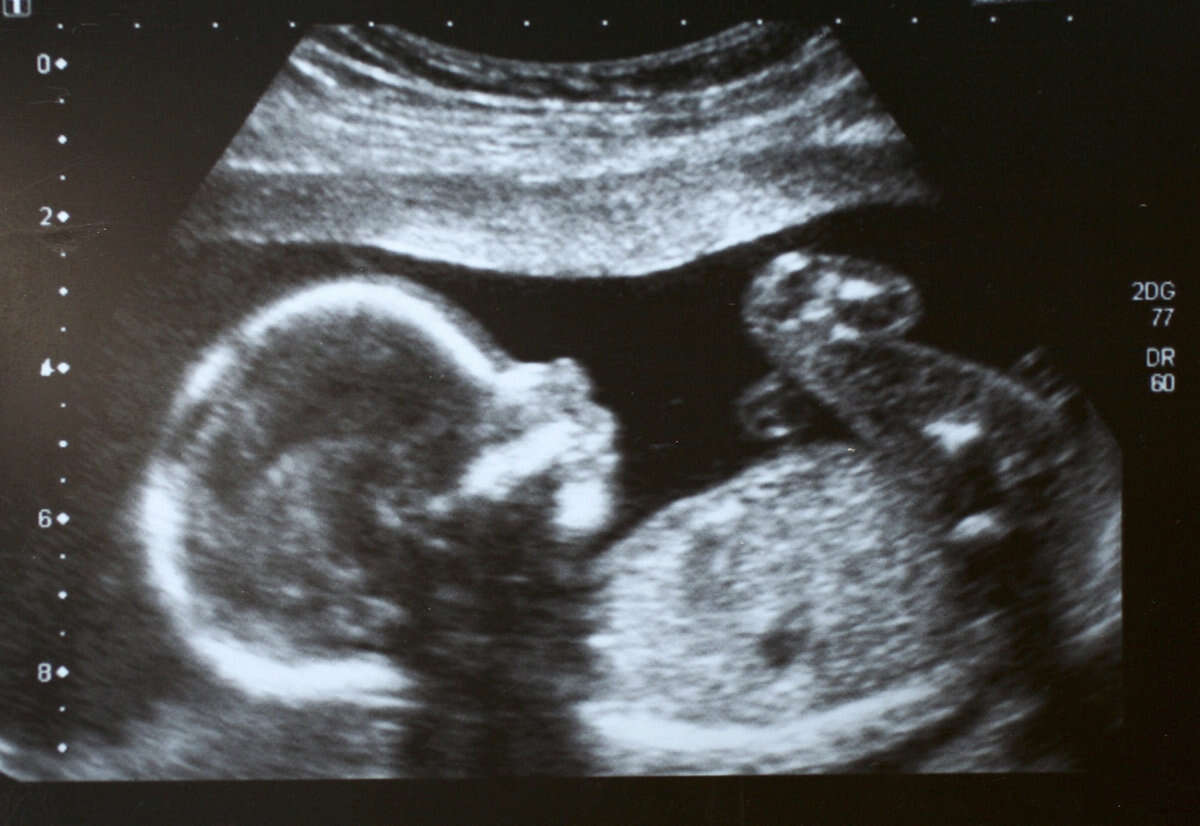

"בתי מדהימה" // צילום (אילוסטרציה): GettyImages